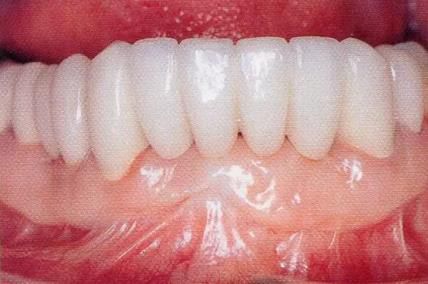

圖16-9    術(shù)后1周。

圖16-10  佩戴最終修復(fù)體時(shí)。